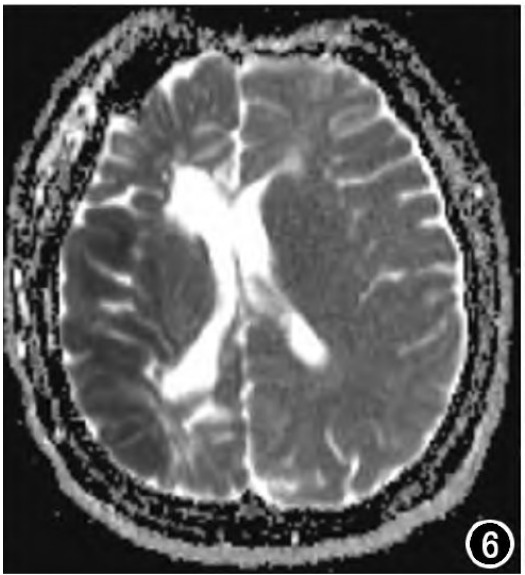

白质低信号(DWM)如何助力医生区分 NKH、MOG 脑炎与硬膜下血肿?